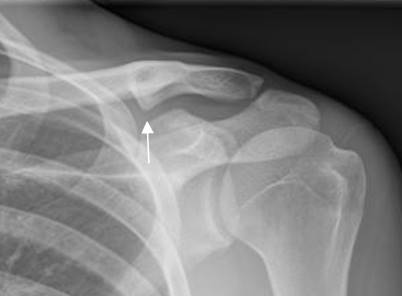

Fig 143. Neuropraxia.

A: RM coronal en T1y B: RM coronal en STIR. Cambios inflamatorios por encima de los vasos subclavios, que rodean las raíces nerviosas, las cuales permanecen integras. La lesión se produjo después de una luxación de hombro.